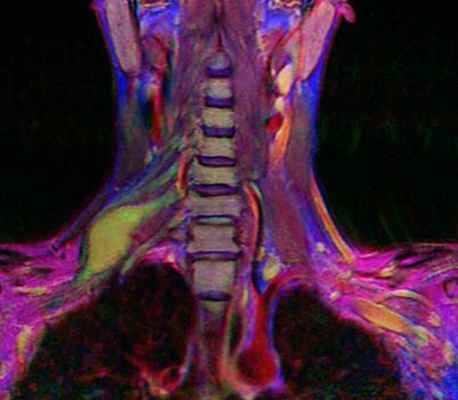

МРТ плечевого сплетения

МРТ мягких тканей шеи. Корональная Т2-взвешенная МРТ. Невринома плечевого сплетения справа. Цветовая обработка изображения.

Плечевой сплетение состоит из тесно переплетающихся нервных стволов, отходящих от вентральных корешков нервов шейного отдела (С5-С7) и грудного отдела (Т1) спинного мозга. 3 первичных ствола неоднократно делятся и взаимно соединяются. Плечевое сплетение, в конечном итоге, переходит в нервы верхних конечностей, обеспечивая чувствительную и двигательную иннервацию. Расположено плечевой сплетение в области ключицы.